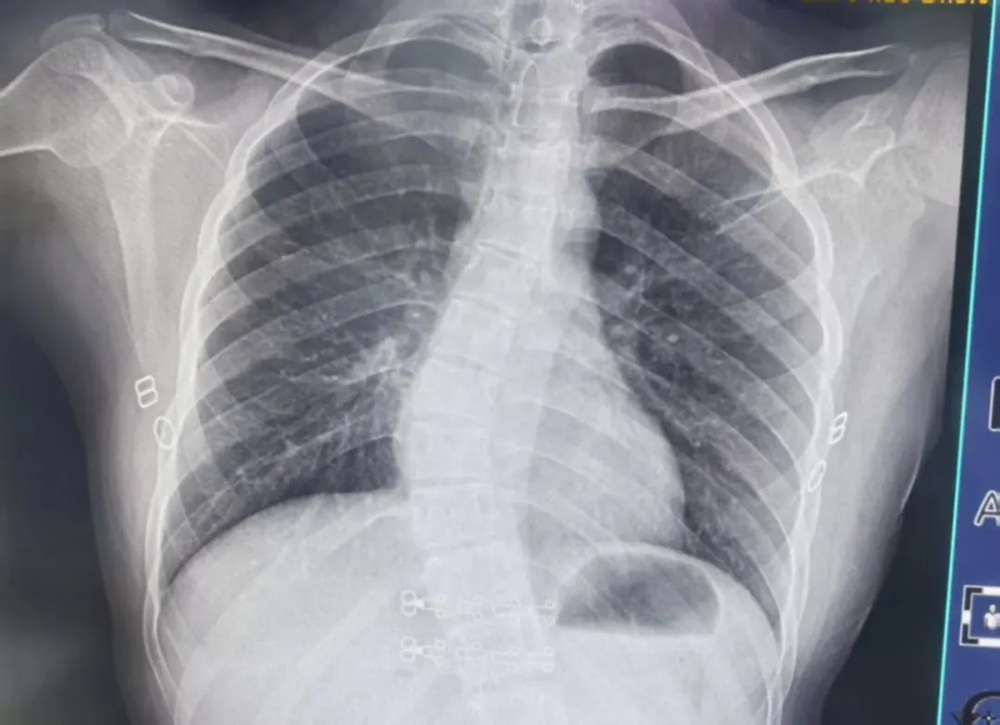

只要发现以上任何一种异常,务必立即带孩子到医院脊柱外科做专业脊柱X光检查,明确侧弯角度,切勿抱有“长大就好了”的侥幸心理。

脊柱是人体最大的支撑,正常情况下,脊柱有4个弯曲,从正面看是直的,侧面看是S形。而脊柱侧凸,俗称脊柱侧弯,是脊柱弯曲异常并伴椎体旋转的三维脊柱畸形,常采用Cobb法测量弯曲角度,大于10°即可确诊。

针对青少年特发性脊柱侧弯的治疗分非手术治疗和手术治疗。非手术治疗主要适用于轻中度脊柱侧弯患者,这部分人群占较高比例,是目前预防和治疗脊柱侧弯不可或缺的方式,包括各类不良姿势纠正、生活习惯调整、特异性运动疗法、旋转成角呼吸训练和支具治疗等。治疗建议:

Cobb角小于5°~10°的患者建议定期观察随访,年度复查一次脊柱X光片;

Cobb角为10°~20°的患者建议接受系统的脊柱姿势评估和各类特异性运动训练,且每隔6个月复查一次脊柱X光片;

Cobb角为20°~40°的患者建议接受系统的脊柱姿势评估、支具治疗和各类特异性运动训练。同时结合骨骼成熟度和侧凸进展状况,合理调整临床和/或影像学随访频率。

Cobb角>40°的患者需要考虑通过手术的方法进行干预。